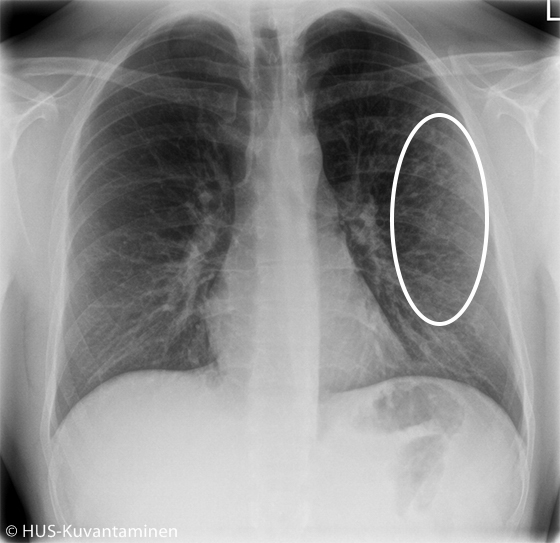

Atypical pneumonia in a patient with HIV (radiograph with markers).

The chest X-ray showed atypical pneumonia. There is diffuse shadowing and increased markings in the distal lung parenchyma (circle).

Picture: HUS Imaging